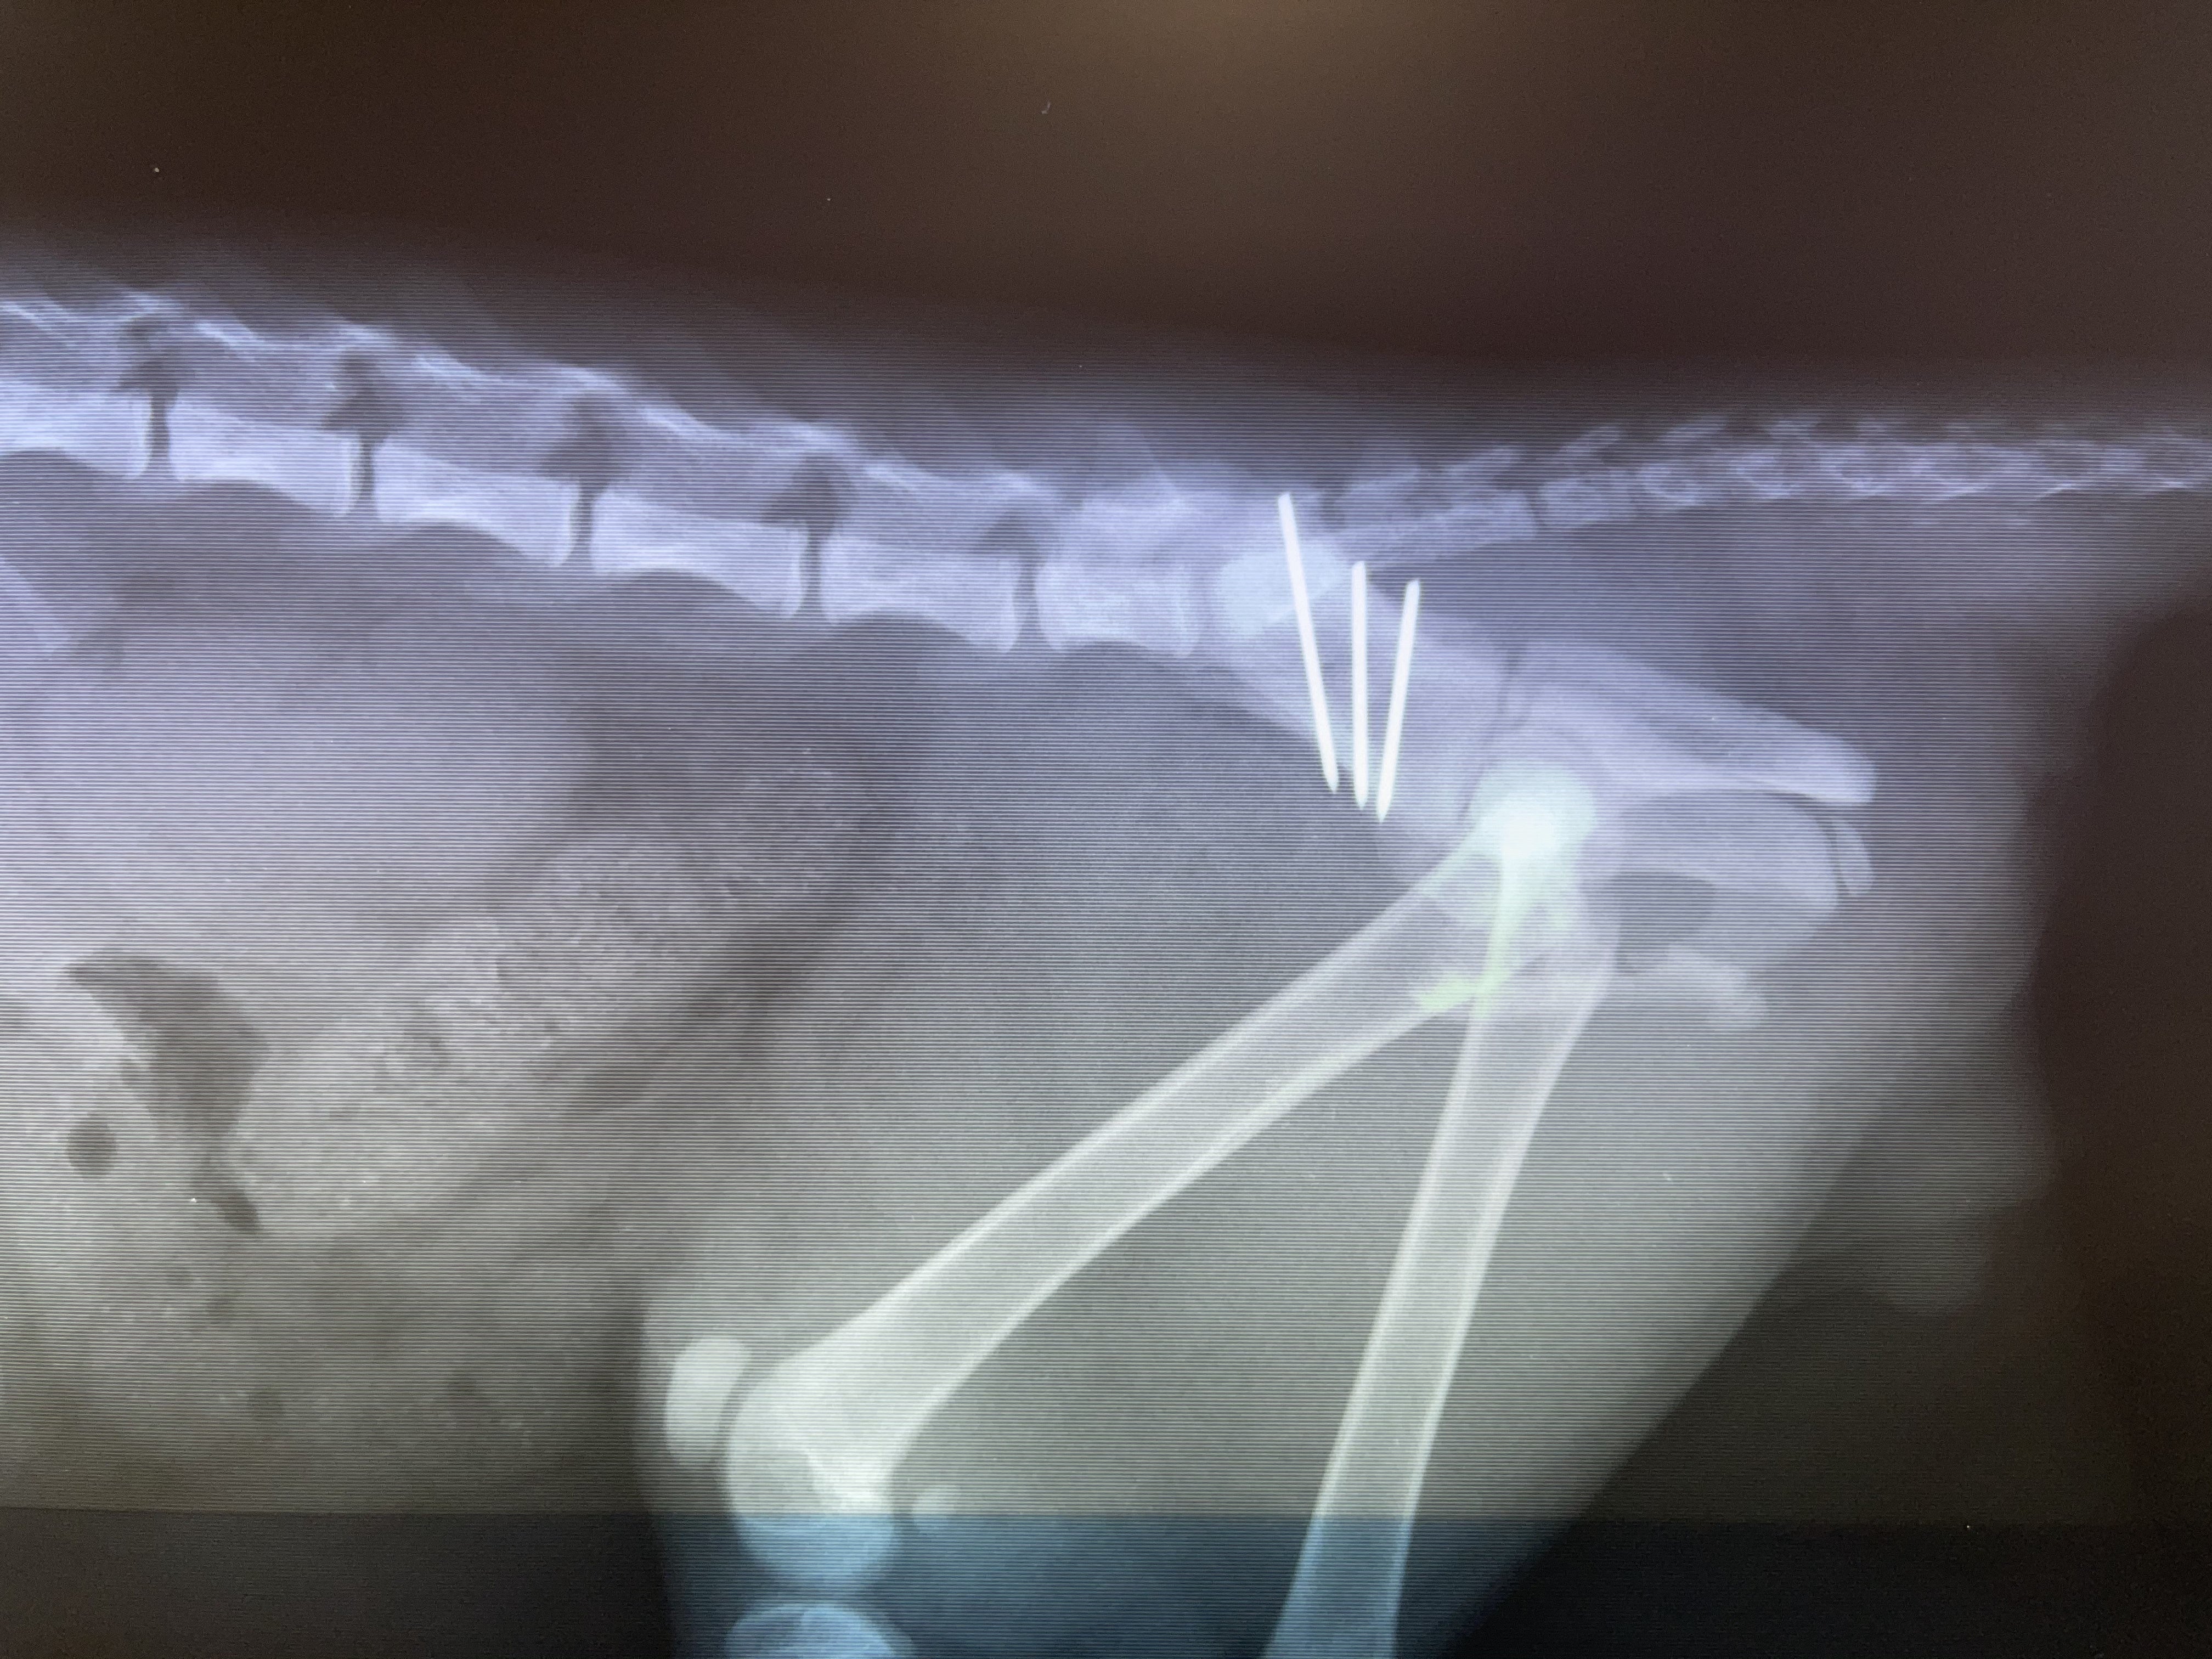

<手術後>

手術後内臓も綺麗です

とても難しい手術だったようです。ありがとうございました!!

1月25日:子猫レントゲンで骨の状態を検査

術後X線検査1回:11,000円